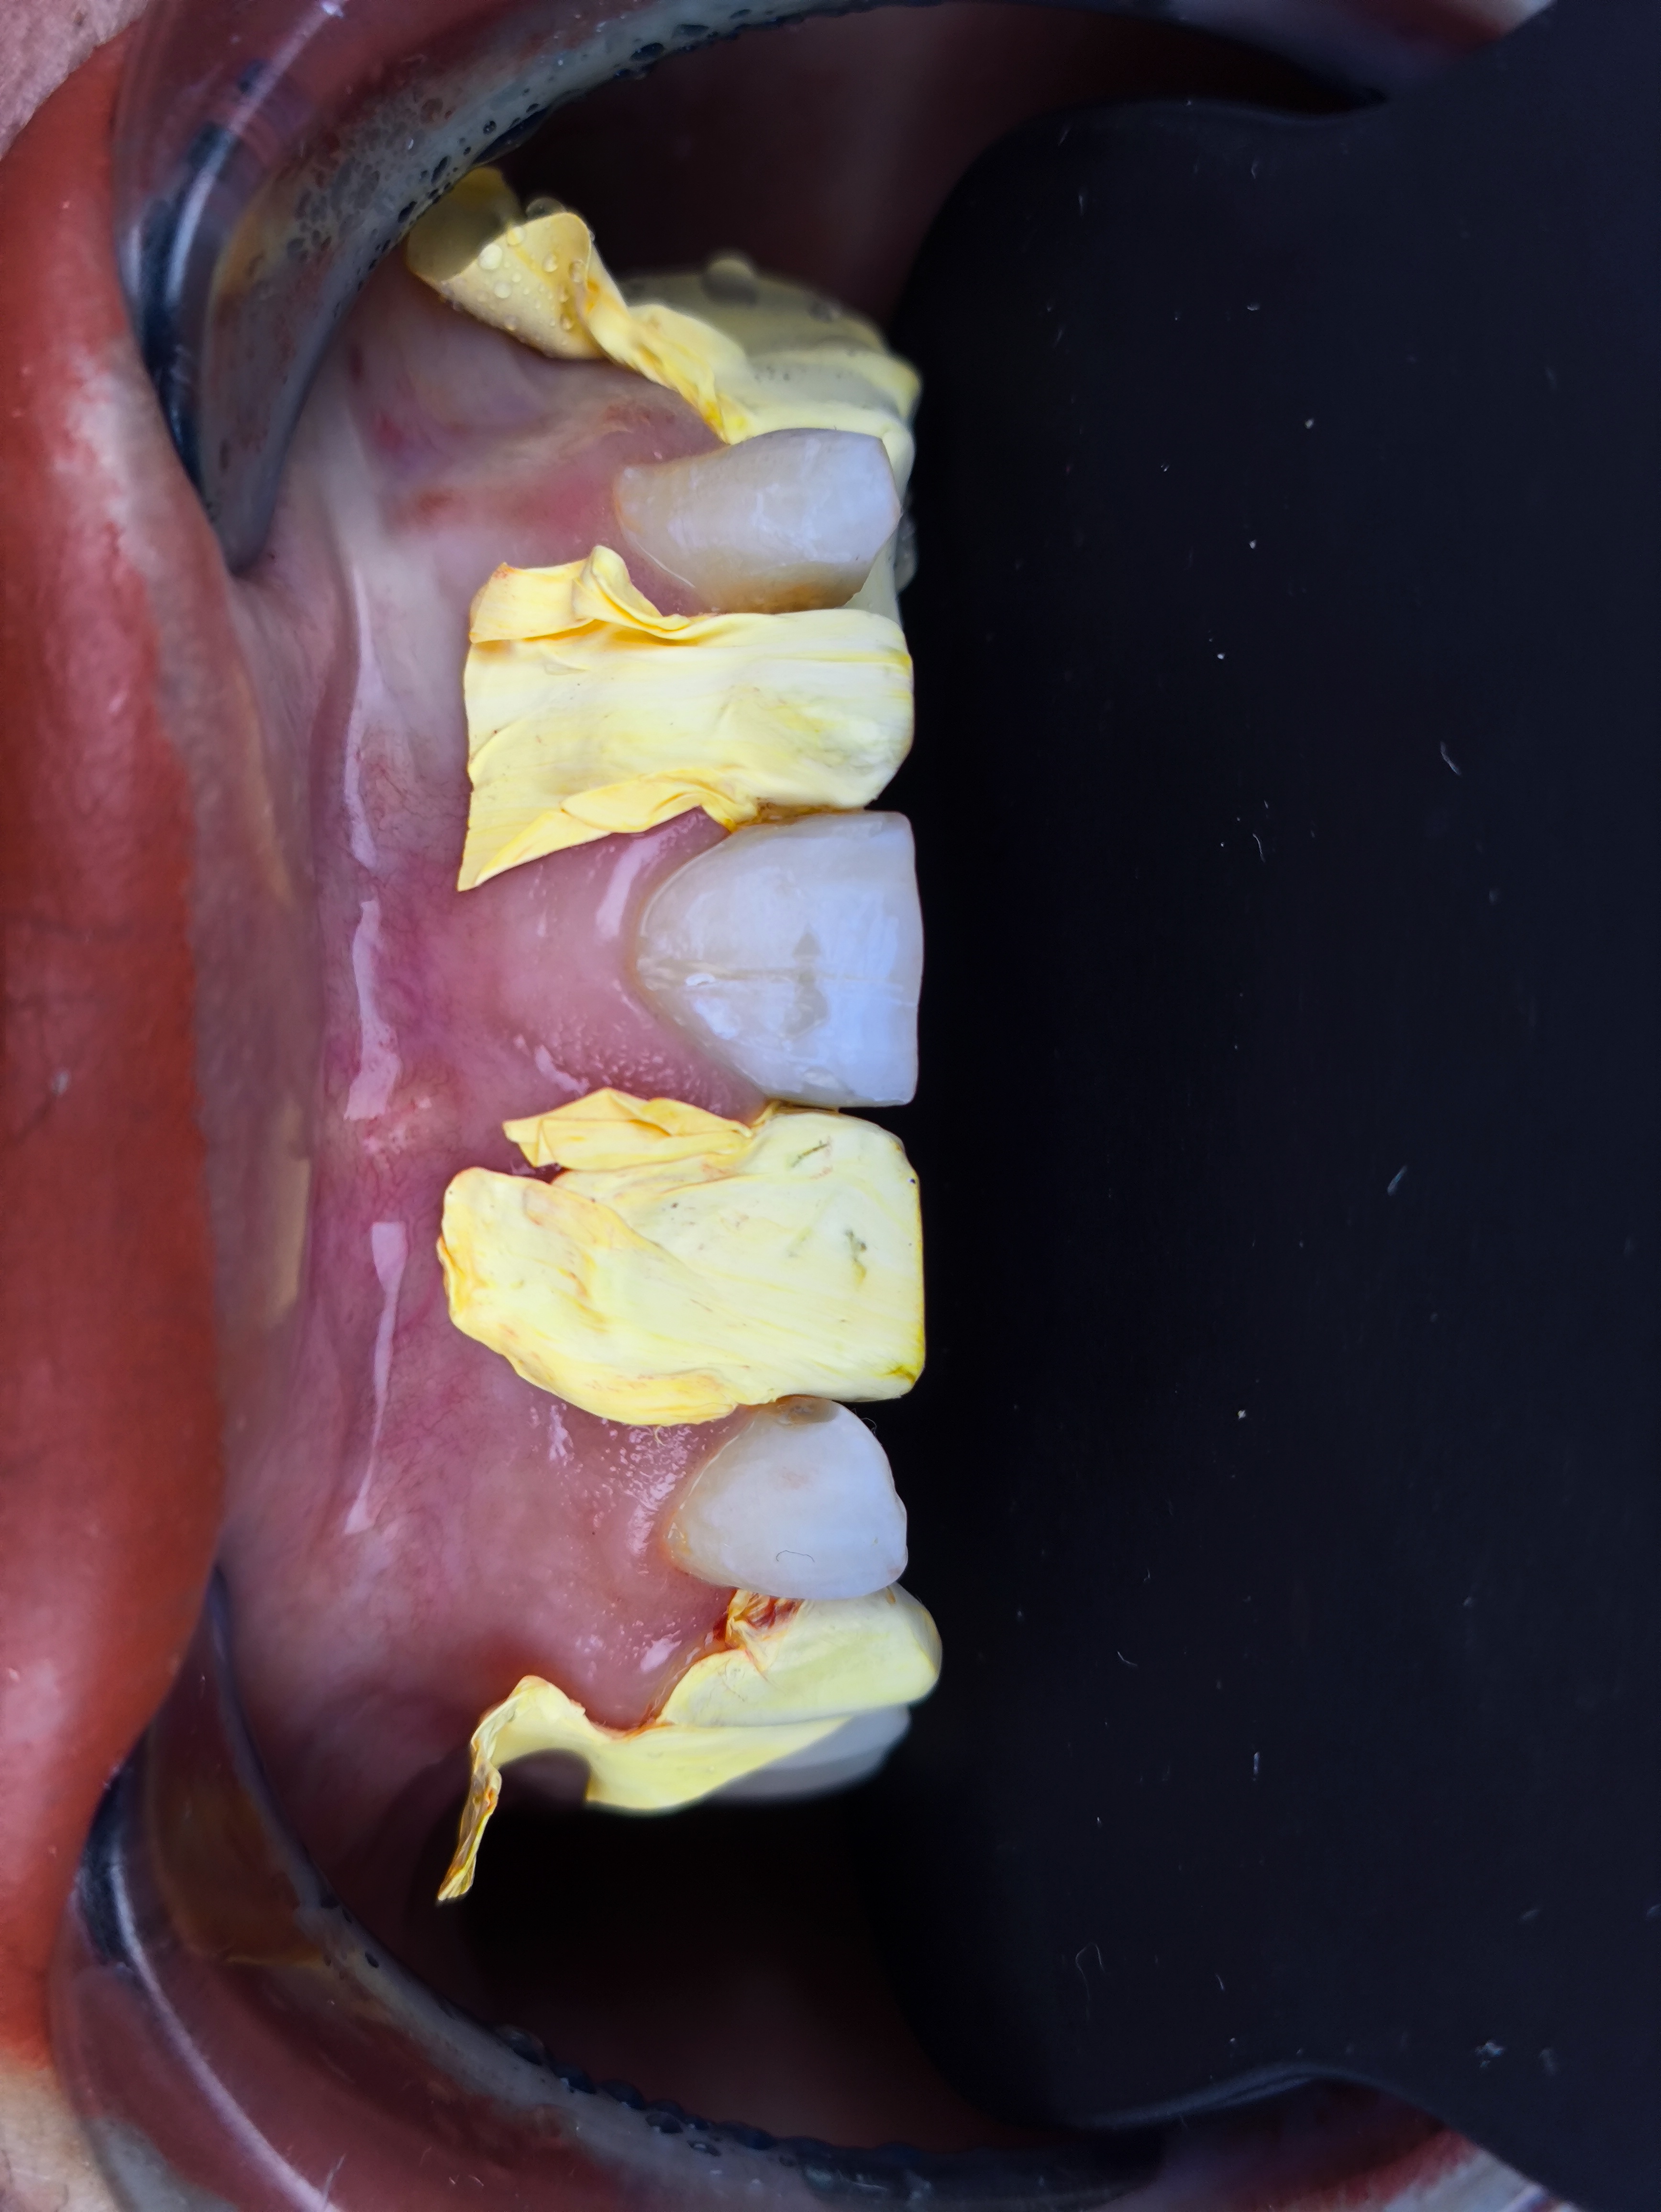

Smile Design Case 4